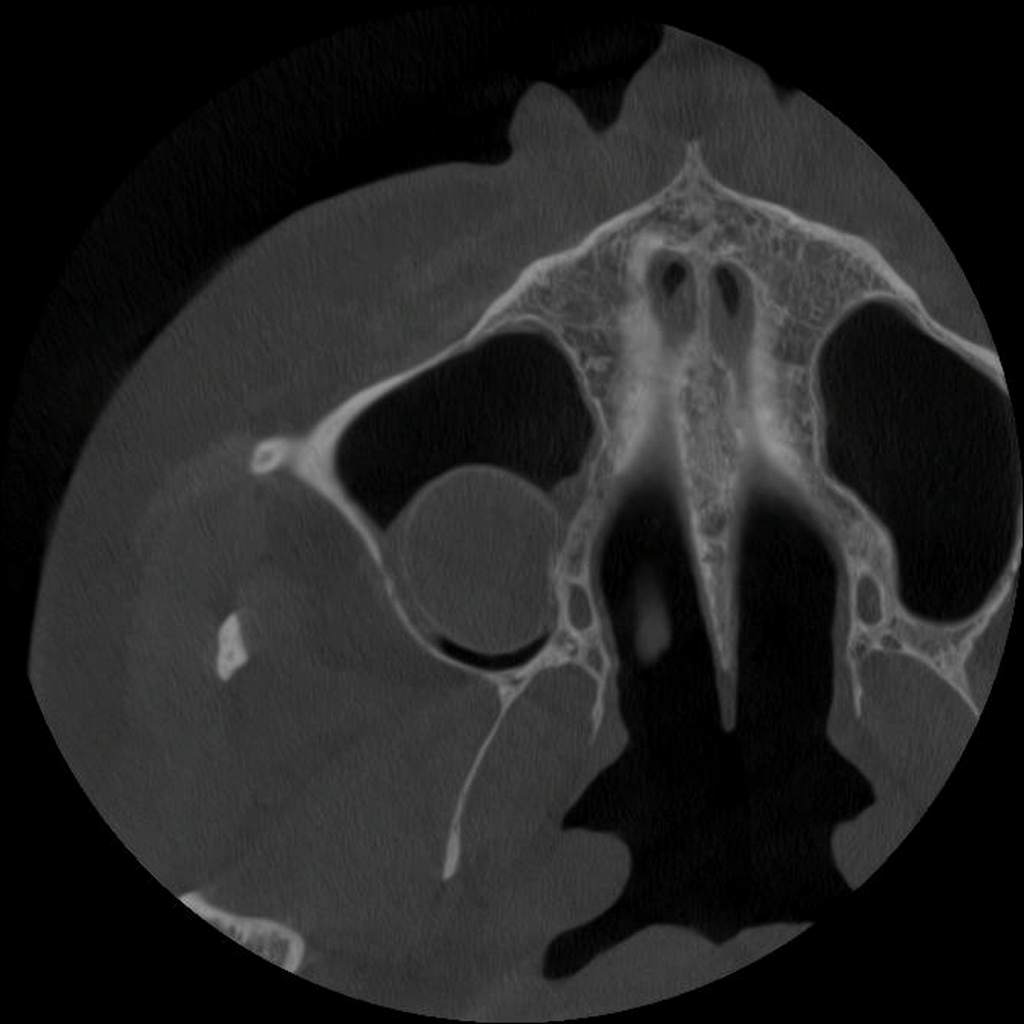

Σήμερα, στο «οπλοστάσιό» μας, έχει προστεθεί και η υπολογιστική τομογραφία κωνικής δέσμης (CBCT), οι εικόνες της οποίας είναι ιδανικές τόσο για να μας πληροφορήσουν για τη μορφολογία του συστήματος των ριζικών σωλήνων αλλά κυρίως να μας βοηθήσουν στη διάγνωση των βλαβών στο άκρο της ρίζας, στην έκταση αυτών των βλαβών και τη σχέση τους με παρακείμενες ανατομικές δομές (π.χ. ιγμόρειο).